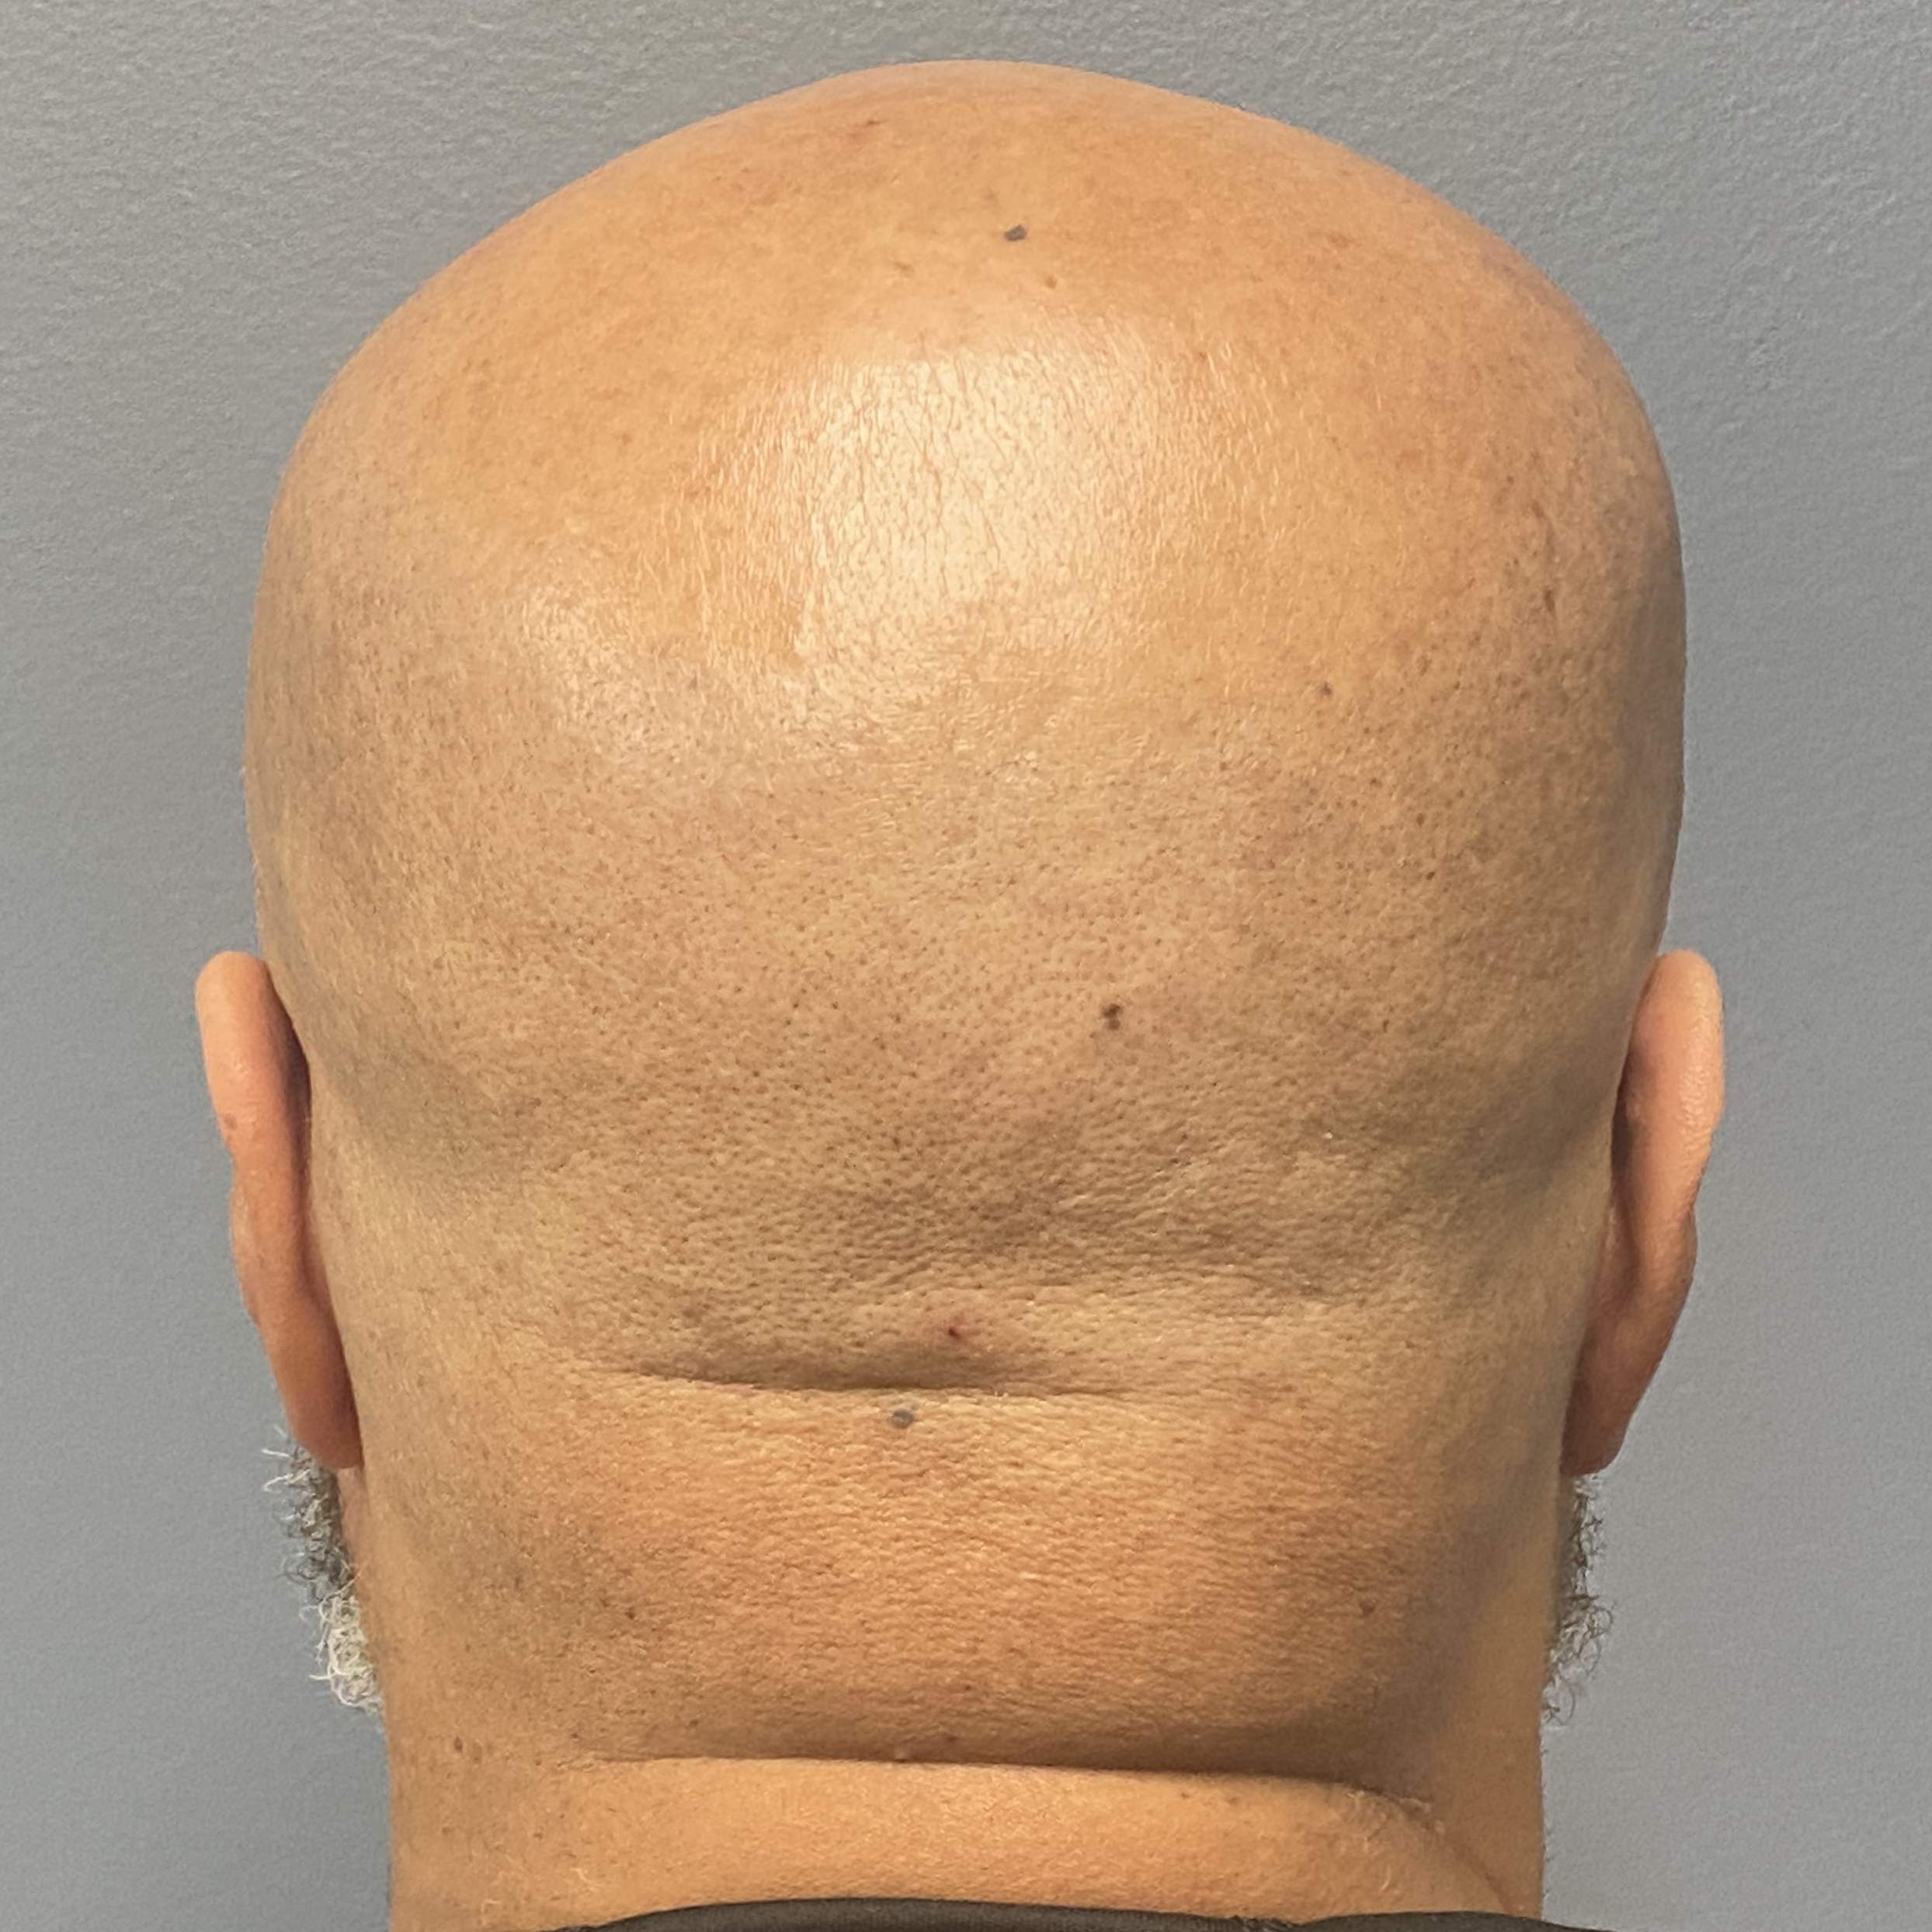

Patient 129

Desire for reduced width/convexity on the sides of his head.

Head narrowing using a temporal muscle transposition technique seen one day postop. He also had an concurrent occipital skull reduction done hence the tape over his incision.

Desire for reduced width/convexity on the sides of his head.

Head narrowing using a temporal muscle transposition technique seen one day postop. He also had an concurrent occipital skull reduction done hence the tape over his incision.